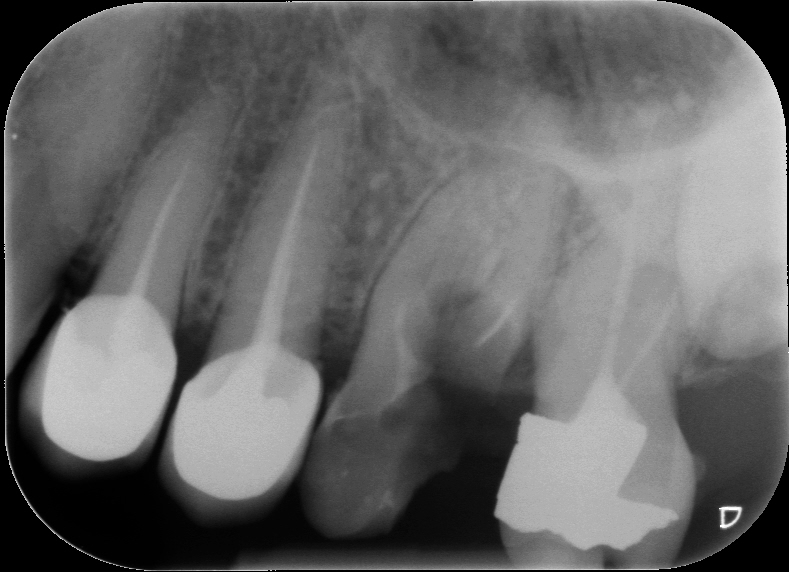

Fig. 2 : Contrôle radiographique en vue d’évaluer l’axe de délogement de la reconstitution corono-radiculaire, ce qui a permis de corriger l’angle de coupe.

D’un point de vue pratique, la première étape consiste à réduire les dimensions du tenon s’il occupe une grande partie de la structure coronaire, de préférence en lui donnant une forme cylindrique similaire à celle d’un tenon préfabriqué. De même, une reconstitution corono-radiculaire coulée ancrée dans plusieurs canaux doit d’abord être sectionnée jusqu’au niveau du plancher de la cavité pulpaire, afin de la traiter comme un ensemble de tenons unitaires, ce qui diminue le degré de rétention global du système. La réduction du tenon doit être effectuée avec des fraises en carbure spécialement conçues pour découper le métal, sous une irrigation abondante. Les évaluations cliniques et radiographies préliminaires sont essentielles pour planifier l’angle de coupe. La procédure doit être fréquemment vérifiée et, si nécessaire, il convient d’effectuer des contrôles radiographiques avant qu’une quantité excessive de dentine ne soit sacrifiée (Figs. 1–3).